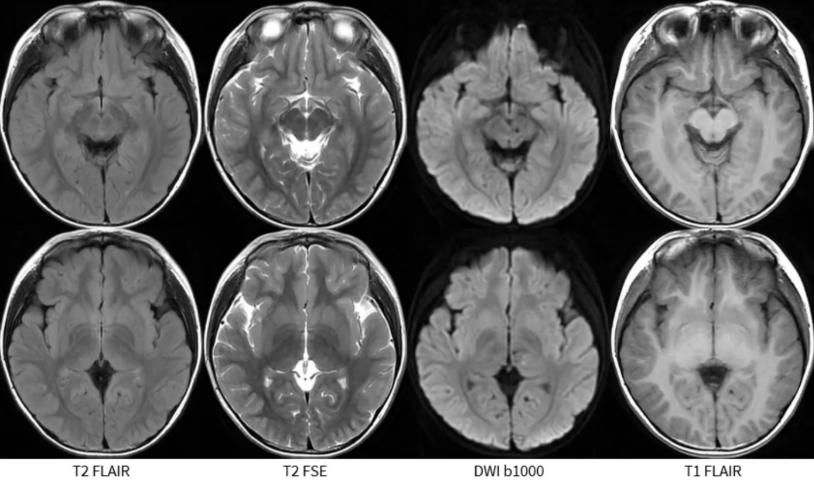

天地良心,无镇静,5岁。 做成这样,还可以了。 T2 FSE和T1 FLAIR稍微有点运动伪影,基本上不耽误诊断。可以接受。 小编本着不着急下班的态度,进去和娃娃交代一句:不要动,闭着眼睛睡觉。

常规序列,好像并没有发现到什么异常信号。

除了

DWI低信号,ADC高信号; DWI稍高信号,ADC略下降。 小朋友,你是否也有很多问号?

接下来,还能搞什么序列。 首先是癫痫经典序列容积CUBE T2FLAIR成像。

并未见到显著异常。 癫痫三大利器:容积T2 FLAIR、容积T1以及高分辨COR T2W。